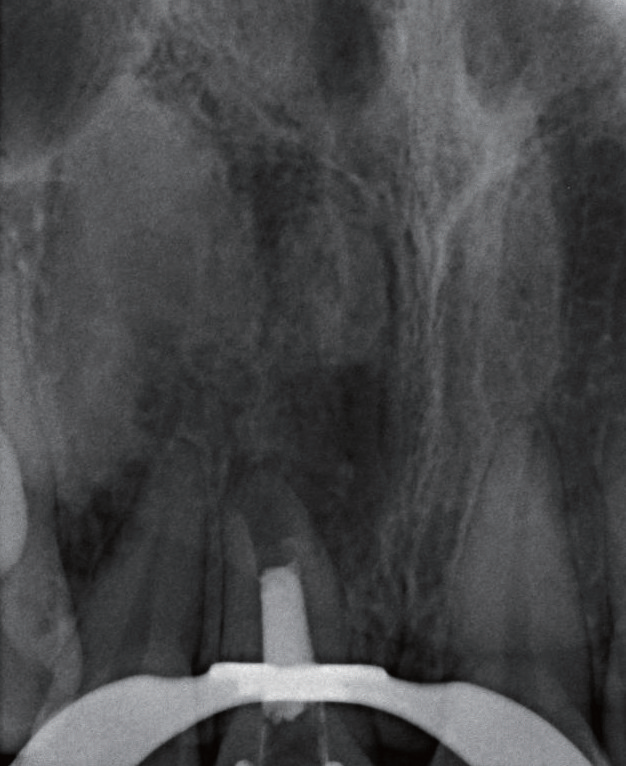

图3 11 根管过于宽大,管壁略显薄弱,牙根长度较短

治疗过程   显微镜下可见11牙冠唇侧(图4)和腭侧(图5)存在数个大小深浅不一的裂纹,开髓至牙本质层(图6),患者表示无任何不适,开髓后就闻到髓腔内有臭味溢出,但患者依然无疼痛,经确认11牙髓已坏死(图7)。随后进行根管预备、次氯酸钠溶液冲洗、纸尖干燥(图8)、试主尖(图9),因根尖呈开口状,决定将牙胶尖四周覆盖MTA进行根尖封闭(图10~12),X线片显示根充密合,后续封闭根管中部和冠部(图13),并用光固化复合树脂充填11牙冠(图14),调磨抛光,再次拍摄根尖X线片确认治疗结果(图15),嘱患者定期复查,观察患牙。

图8 11根管预备后用牙胶尖探出根尖口,发现根尖病灶区里虽无脓液也无新鲜血液

图9 由于11 根尖未闭合,试主尖时始终得不到理想回拉阻力